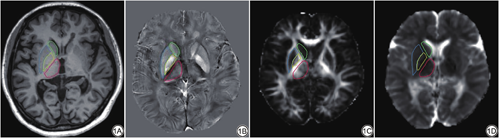

WM-LV在3D-FLAIR序列中测量,由2名5年以上MR研究经验的医师基于ITK-SNAP (Version 3.8;http://www.itksnap.org/pmwiki/pmwiki.php)软件在RRMS患者的3D-FLAIR序列上逐层勾画白质病灶测得体积,重复勾画两次,其体积通过组内相关系数检验(ICC=0.963,P<0.001),取平均值为该患者WM-LV;基于MATLAB R2013b (Version 8.2.0.701)平台的SPM 8 (Version 6313;https://www.fil.ion.ucl.ac.uk/spm/software/spm8/)的VBM对3D-T1WI数据进行预处理,随后基于REST软件,以双侧尾状核、壳核、苍白球、丘脑为感兴趣区(region of interest,ROI) (图1A),提取各核团体积。

QSM图像重建是基于MATLAB平台的STISuite (Version 3.03;http://people.eecs.berkeley.edu/~chunlei.liu/software.html)软件,步骤包括场图拟合、相位解缠绕、背景场去除、磁化率反演;DTI图像重建是基于FSL (Version 5.0.10;https://fsl.fmrib.ox.ac.uk/fsl/fslwiki/)软件,经过b0像配准、头动及涡流校正、张量计算得到各向异性分数(fractional anisotropy,FA)和平均扩散率(mean diffusivity,MD)图。随后基于FSL软件将个体空间QSM及FA、MD图配准至蒙特利尔神经病学研究所(Montreal Neurological Institute,MNI)标准空间坐标,以相同ROI提取各核团定量磁化率值(quantitative susceptibility value,QSV)及FA和MD值(图1B~1D)。